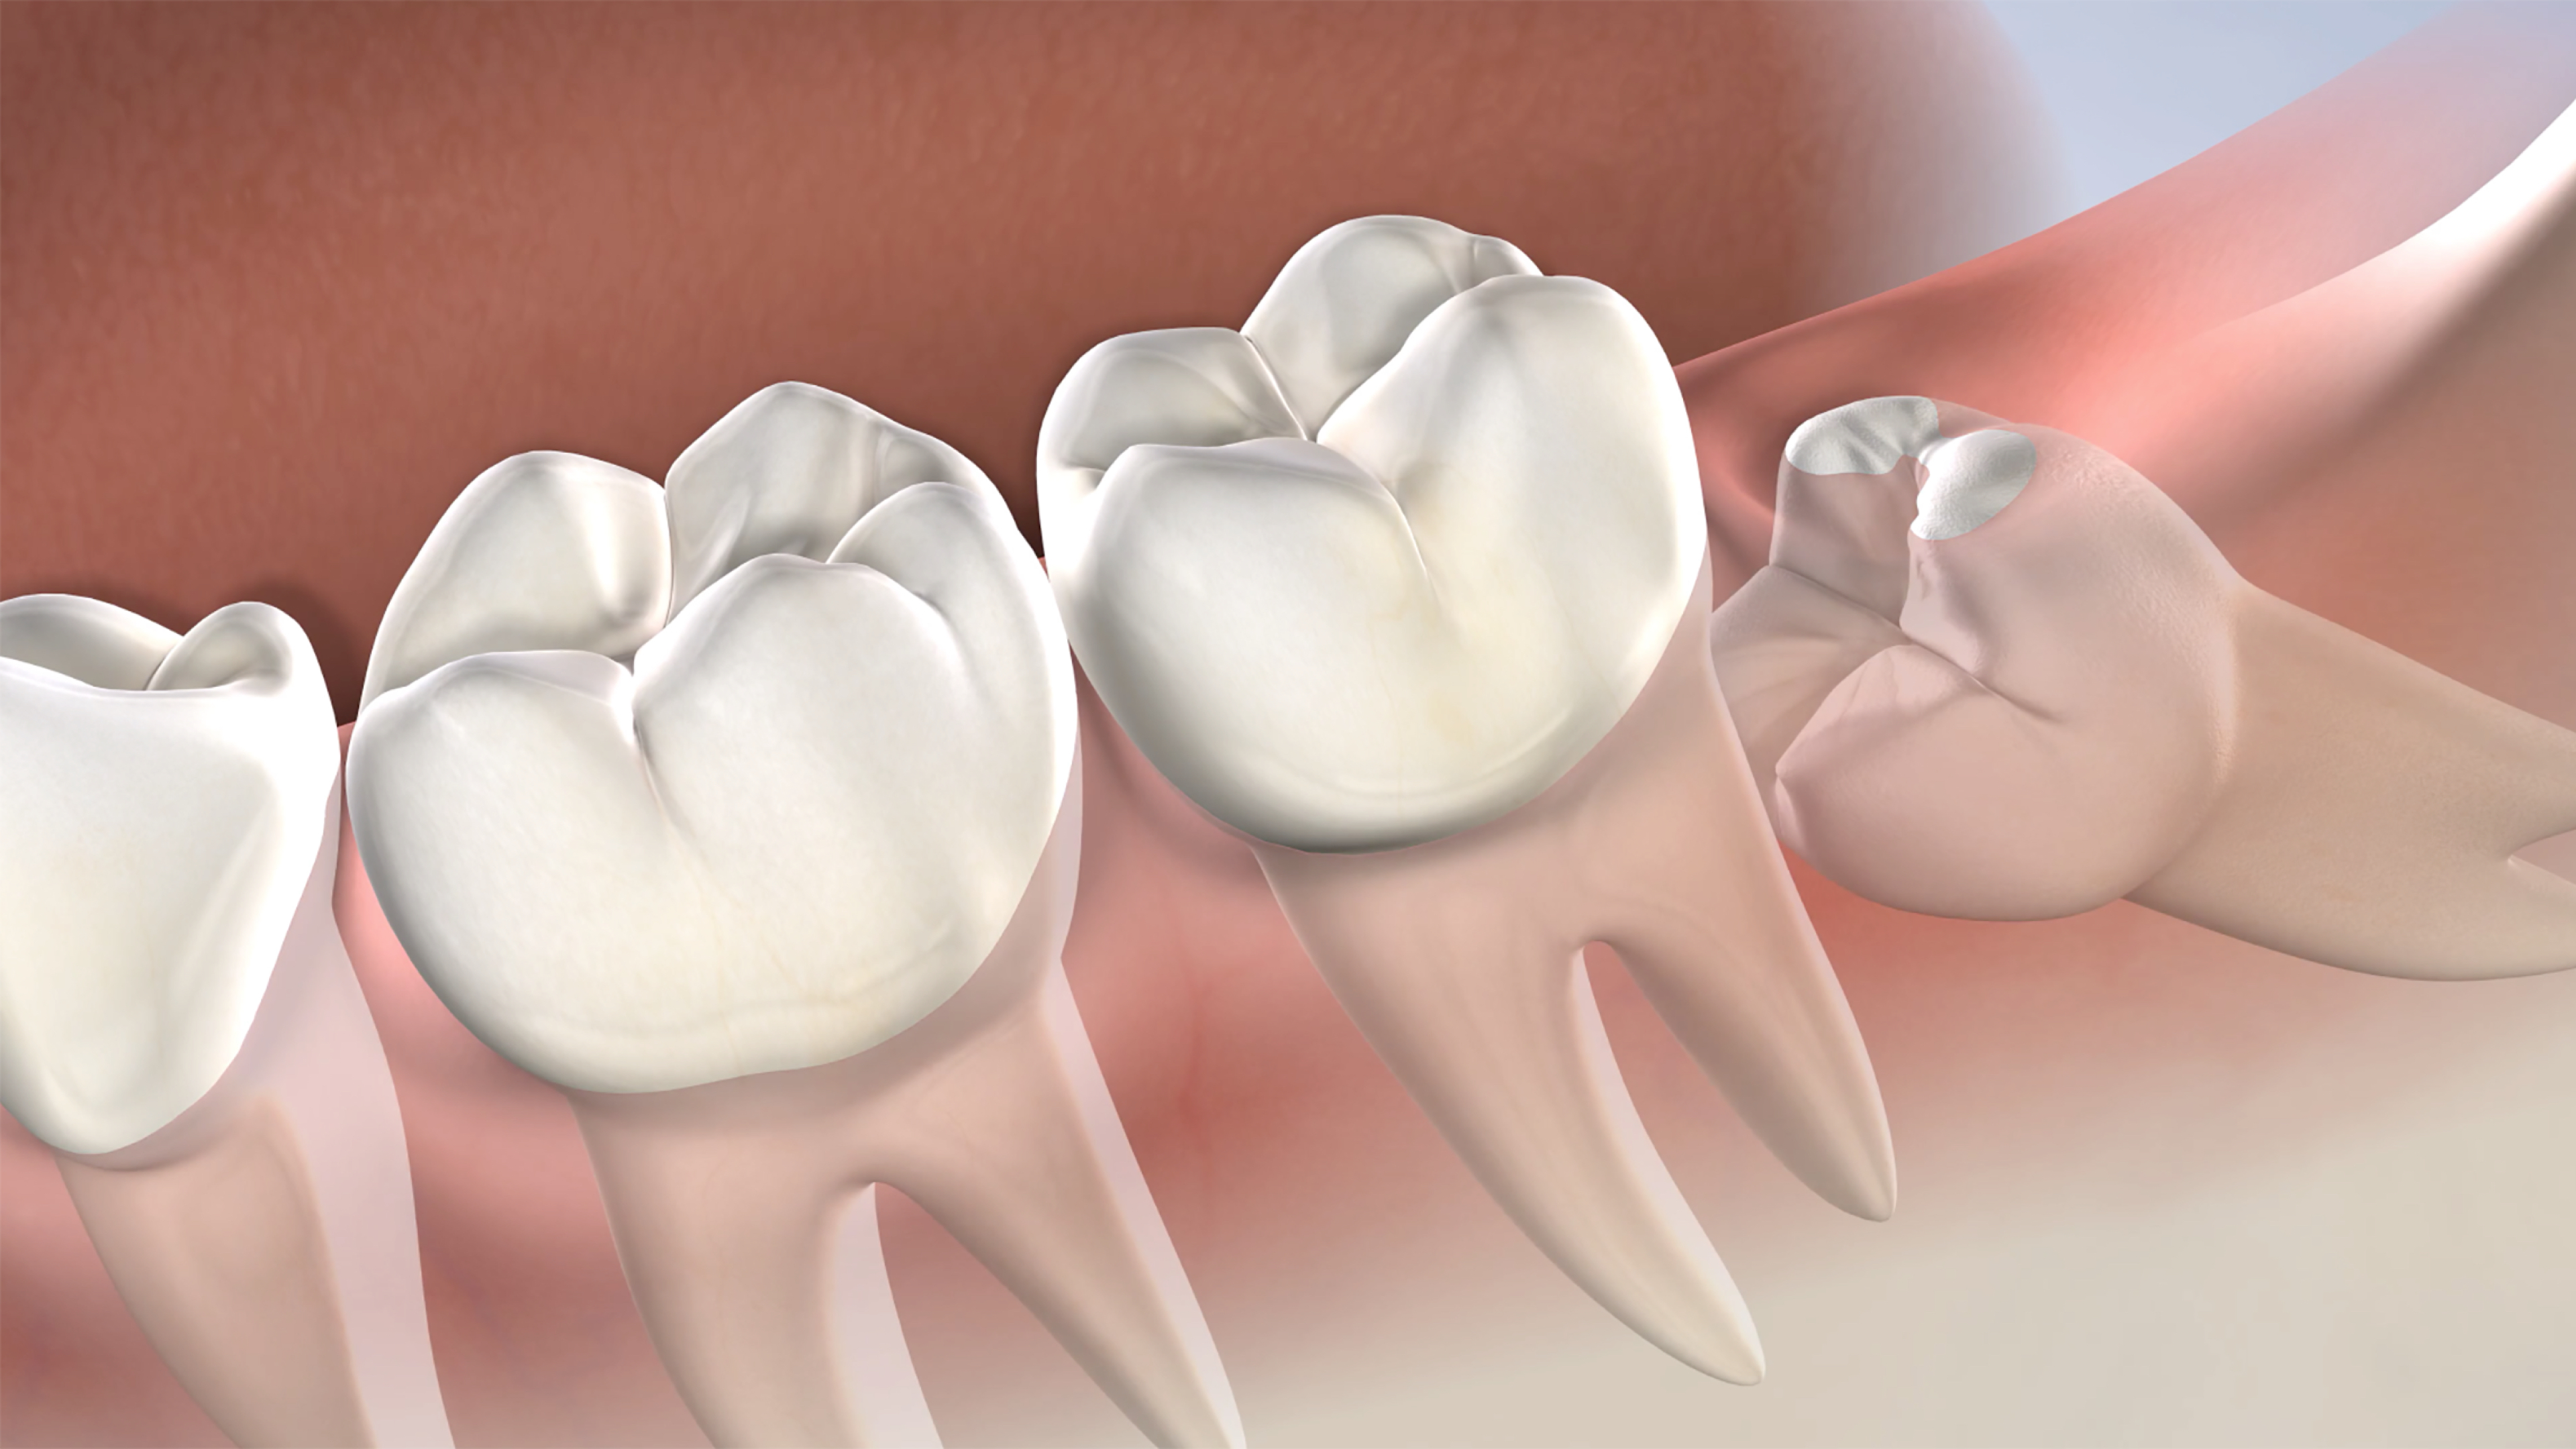

حشو و تركيبات